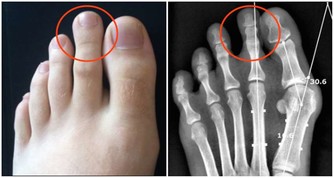

(2)太衝穴

點按太衝穴也可以幫助消氣。另外,肝陽上亢的高血壓患者,平時也可經常點揉腳上的這個穴位。

太衝穴位於足背側,第一、二蹠骨結合部之前凹陷處。